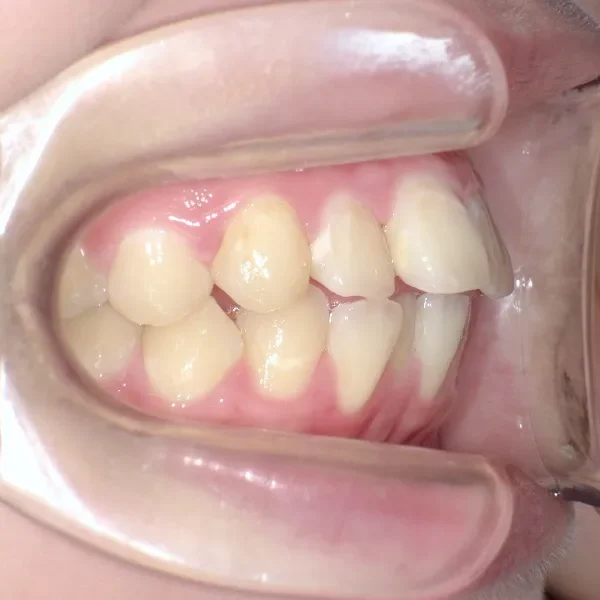

治療経過1

再治療の時は、上の歯は前から見えにくいオリジナル固定装置、下の歯はマルチブラケット装置を使用し、治療しました。

治療回数62回、1年6ヶ月の治療期間で矯正治療を終了しました。

前回の治療で歯の根っこの部分の位置を治していたので、全部前から付けるのではなく最低限見える装置で治せました。